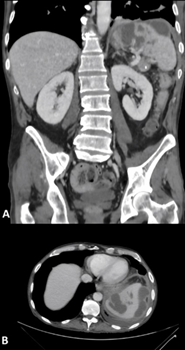

(Figure

1A, 1B) shows contrast-enhanced abdominopelvic CT scans revealing

heterogeneous splenomegaly with multiple hypodense, poorly enhancing

parenchymal lesions, suggestive of splenic infarctions or collections of

indeterminate nature.

Figure 1: Splenic lesions observed on CT scan